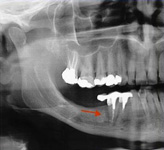

Onemocnění parodontu patří ke druhému nejčastějšímu onemocnění v dutině ústní, ihned po zubním kazu. Nejčastějším problémem je gingivitis- zánět dásní a také parodontitis - zánětlivé onemocnění postihující závěsný aparát zubů, přilehlou dáseň i kost. Mezi časné projevy gingivitidy patří krvácení dásní, které může v případě parodontitidy přejít ve tvorbu parodontálních chobotů, spojené se zápachem z úst, tvorbou hnisu, bolestmi a viklavostí zubů v důsledku ztráty kosti. Tomuto onemocnění se dá úspěšně předcházet pravidelnými kontrolami, sanací chrupu a péčí v rámci dentální hygieny.

Používá se i v implantologii, při stanovení diagnózy a léčby periimplantitidy (zánětu měkkých tkání a kosti v okolí implantátu).